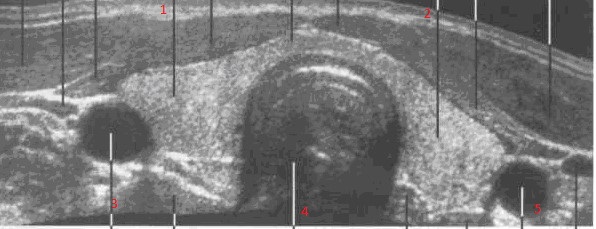

Рис. 24. Сонограммаражение щитовидной железы на уровне перешейка:

1- правая доля ЩЖ , 2- левая доля ЩЖ, 3- правая общая сонная артерия, 4- трахея, 5- левая  общая сонная артерия